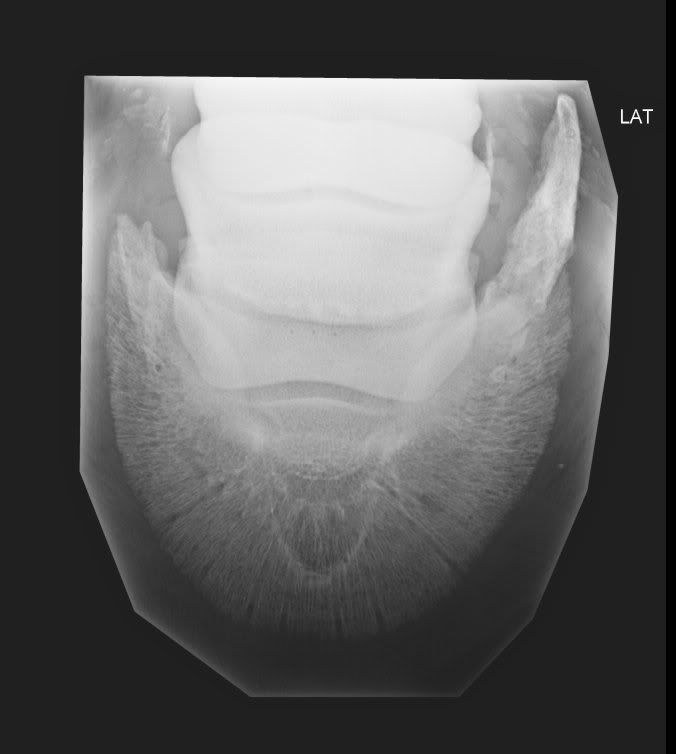

Calcaneus Fractures Core EM Pedal Fracture Definition This bone, which is rough and pitted in texture, is surrounded by the. Fractures of the distal phalanx (pedal bone) usually occur as a result of trauma such as kicking a solid object, standing on a stone or fast exercise on hard ground. Treatment can be nonoperative or operative. Looking for online definition of pedal fracture in the medical dictionary?. Pedal Fracture Definition.

From coreem.net